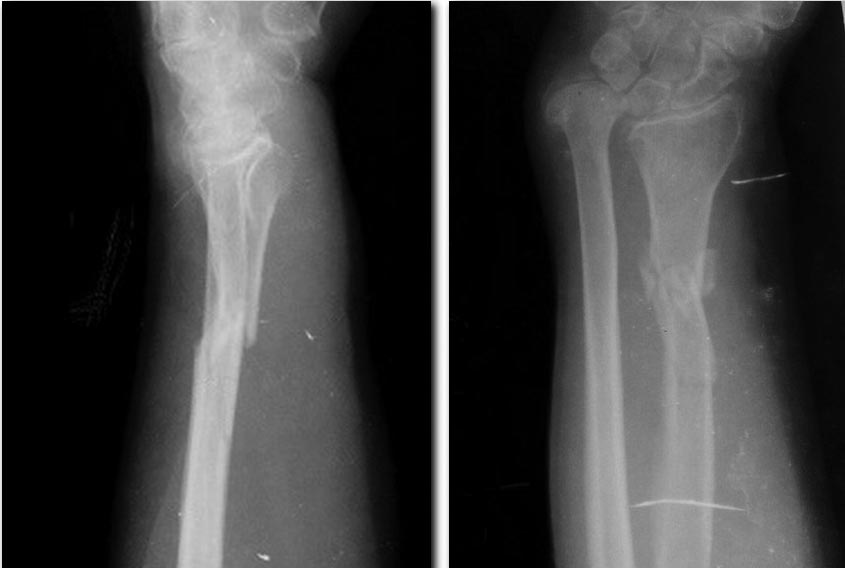

[Ortho] Приобретенная косорукость

Рентгенограммы